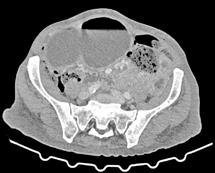

A las 36 horas de vida presenta nuevo empeoramiento respiratorio, se solicita estudio completo y se realiza punción lumbar (a pesar de paráme tros infecciosos negativos en la analítica). Se obtiene líquido purulento y se procede a escalada de tratamiento a ceftriaxona y ampicilina (mantiene tratamiento durante 7 y 3 días respectivamente, no aislándose microorga nismos en muestras de líquido cefalorraquídeo ni hemocultivos). Se repite la radiografía de tórax en la que se evidencia neumotórax de nueva apa rición e imagen sugestiva de neumomediastino. Ante estos hallazgos, se solicita TC de tórax que confirma el diagnóstico y descarta la existencia de causas desencadenantes (Figura 2). Se mantienen requerimientos de VMNI durante 4 días más, siendo finalmente posible la desescalada gradual a oxigenoterapia con gafas nasales durante 4 días. Se consigue retirada del soporte respiratorio de manera completa pasados 8 días, realizando un control con TC de tórax a los 9 días de vida (Figura 3) que muestra mejoría significativa acompañándose de una recuperación clínica completa.

Pese a no existir consenso, la radiografía de tórax suele ser la prueba radiológica de elección (6). En nuestro paciente, la radiografía de tórax orientó el diagnóstico. Para ompletar el estudio y descartar posibles causas desencadenantes, se decidió realizar una TC torácica simple (sin la administración intravenosa de contraste). De acuerdo al protocolo de nuestro centro, se ajustaron los parámetros de corriente y potencial del tubo para pacientes pediátricos, con algoritmos de reconstrucción iterativa que per miten reducir el ruido de la imagen (la dosis efectiva fue de 0,019 mSv, equivalente a la de una radiografía de tórax).

Figura 2. (Izq.) radiografía de tórax en proyección AP a las 36 horas de vida donde se objetiva neumotórax de nueva aparición (flechas azules) y una zona de hiperclaridad alrededor de la silueta cardíaca que sugiere importante neumomediastino (estrellas amarillas). (Der.) TC de tórax sin contraste intravenoso en ventana de pulmón que confirma la presencia de neumomediastino (estrella amarilla). Se objetivan focos de consolidación periféricos y bandas lineales de densidad aire paralelas y adyacentes a las vainas broncovasculares (flechas amarillas).